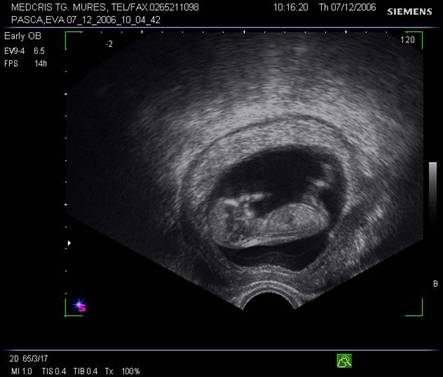

Fig. nr.108. Sarcina 7 saptamani la ecografia abdominala.